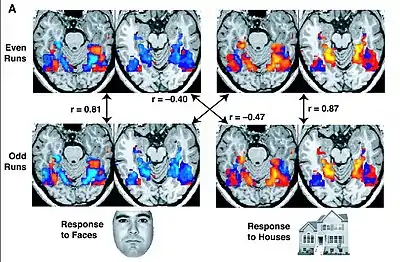

L’IRMf est parfois considérée par ses détracteurs comme une forme moderne de la phrénologie, cette théorie qui considère que les bosses du crâne sont le reflet du caractère d’une personne[5]. Les belles images obtenues par l’IRMf lui valent aussi le surnom de « blobology », « la science des taches de couleur », en ce sens que la technique permet bel et bien de savoir, par exemple, qu’une tâche langagière est corrélée avec une activation dans l’hémisphère gauche, mais sans confirmer que cette activation est due, par exemple, directement au traitement du langage ou plutôt au simple fait de porter attention à un écran. Selon Peter Bandettini, on ne peut pas inférer une causalité simplement parce qu’on connait l’endroit d’activation[9]. Plutôt que de simplement observer des tâches, certains chercheurs utilisent plutôt l’analyse multivariée qui permet d’analyser le comportement d’unités plus petites que les tâches : les voxels. De cette façon, des informations qui ne semblaient être que du bruit se transforment en signal[9].

Si l'IRMf permet de localiser dans un cerveau les zones activées par la réalisation d’une tâche simple, il faut cependant interpréter de façon adéquate les résultats. Une fois obtenues les images anatomiques et fonctionnelles du cerveau, elles doivent être traitées pour éliminer les faux positifs et les faux négatifs : « Les images anatomiques pour chaque sujet sont réalignées pour corriger le mouvement du sujet, puis sont alors co-enregistrées avec l’image fonctionnelle. L'analyse statistique permet de détecter les secteurs qui ont été significativement activés lors de l'expérience » [3]. Les images fonctionnelles peuvent être alignées sur une image anatomique individuelle ou encore sur un modèle anatomique moyen, qui représente un cerveau moyen intersujets. Ces images fonctionnelles dépendent du protocole qui est utilisé pour activer le cerveau, et donc pour isoler l’activité cérébrale qu’on veut observer[3]. Dans des protocoles expérimentaux simples, on peut utiliser le paradigme en bloc dit de soustraction ou de différence. « L’activité cérébrale est enregistrée au cours d’une condition neutre (ou de référence R) où le stimulus est présenté sans instruction particulière. Un deuxième enregistrement est effectué mais dans la condition dite cible. L’activité résultant de l’opération étudiée correspond à la « soustraction » de la mesure en condition cible par la mesure en condition neutre. Cette soustraction correspond à un test de différence statistique significative (test T par exemple) appliqué voxel à voxel et dont on peut faire varier le seuil »[3]. Étant donné que le cerveau n’est jamais dans un état d’activation complètement stable, il y a de bonnes chances de retrouver des artéfacts dans les données.